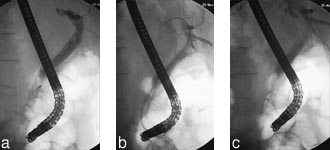

Vår preliminære erfaring med siste generasjon wallstent bekrefter både dens enkle applikasjon og dens gode funksjonstid ved bruk i galleveier (17). Med introduksjonskateter på 8 F kan man bruke standard duodenoskop, og sjansen for å komme gjennom trang striktur er den samme som for plaststent med samme diameter. Våre ti første stentinnleggelser var alle teknisk vellykket og uten prosedyrerelaterte komplikasjoner. Vi valgte å utføre papillotomi før innleggelsen for å sikre full ekspansjon samt god gjennomstrømning av galle i stenten i papillenivå. Wallstent er nå enkel å utløse gjennom duodenoskopet. Full kontroll og med eventuell reposisjonering av stenten når denne forkortes under ekspansjon, kan skje uten problemer. Dette er viktig, da en ekspandert wallstent ikke lar seg fjerne eller reposisjonere etter ferdig applikasjon.